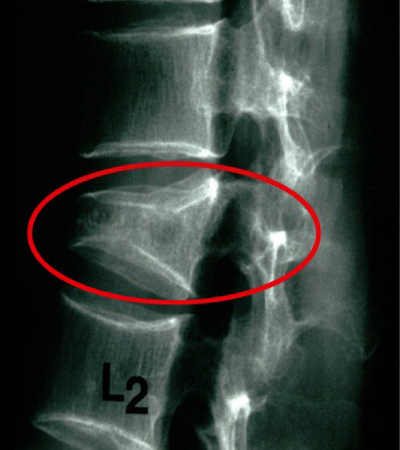

Η οστεοπόρωση είναι μια σιωπηρή νόσος, δεν παρουσιάζει συμπτώματα για μεγάλο χρονικό διάστημα. Αυτό σημαίνει ότι περνάνε αρκετά χρόνια, κατά τη διάρκεια των οποίων η οστεοπόρωση συνεχώς χειροτερεύει από πλευράς απώλειας οστικής μάζας και διαταραχής της μικροαρχιτεκτονικής δομής των οστών, μέχρι να εμφανιστεί το πρώτο της σύμπτωμα, που είναι το κάταγμα. Η οστεοπόρωση είναι νόσος όλων των οστών και γι’ αυτό κατάγματα μπορεί να συμβούν σε διάφορες θέσεις του σκελετού, αλλά συνήθως συμβαίνουν στους σπονδύλους, στον αυχένα του μηριαίου οστού και στο αντιβράχιο. Πιο συγκεκριμένα, περίπου 40% των οστεοπορωτικών καταγμάτων αφορούν τη σπονδυλική στήλη, 20% τον αυχένα του μηριαίου οστού, 20% το αντιβράχιο και 20% διάφορα άλλα οστά. Τα κατάγματα του αυχένα του μηριαίου οστού και του αντιβραχίου συμβαίνουν πάντοτε μετά από έναν χαμηλής βίας τραυματισμό, όπως είναι η πτώση από την όρθια θέση, ενώ συνοδεύονται πάντοτε από πόνο. Αντίθετα, τα σπονδυλικά κατάγματα συμβαίνουν συχνά χωρίς να προηγηθεί τραυματισμός και αρκετές φορές δεν συνοδεύονται από πόνο στη ράχη ή στη μέση παρά μονάχα από ένα ελαφρύ αίσθημα καύσου. Απώλεια ύψους και κύφωση αποτελούν όψιμες εκδηλώσεις της οστεοπόρωσης και οφείλονται σε σπονδυλικά κατάγματα.